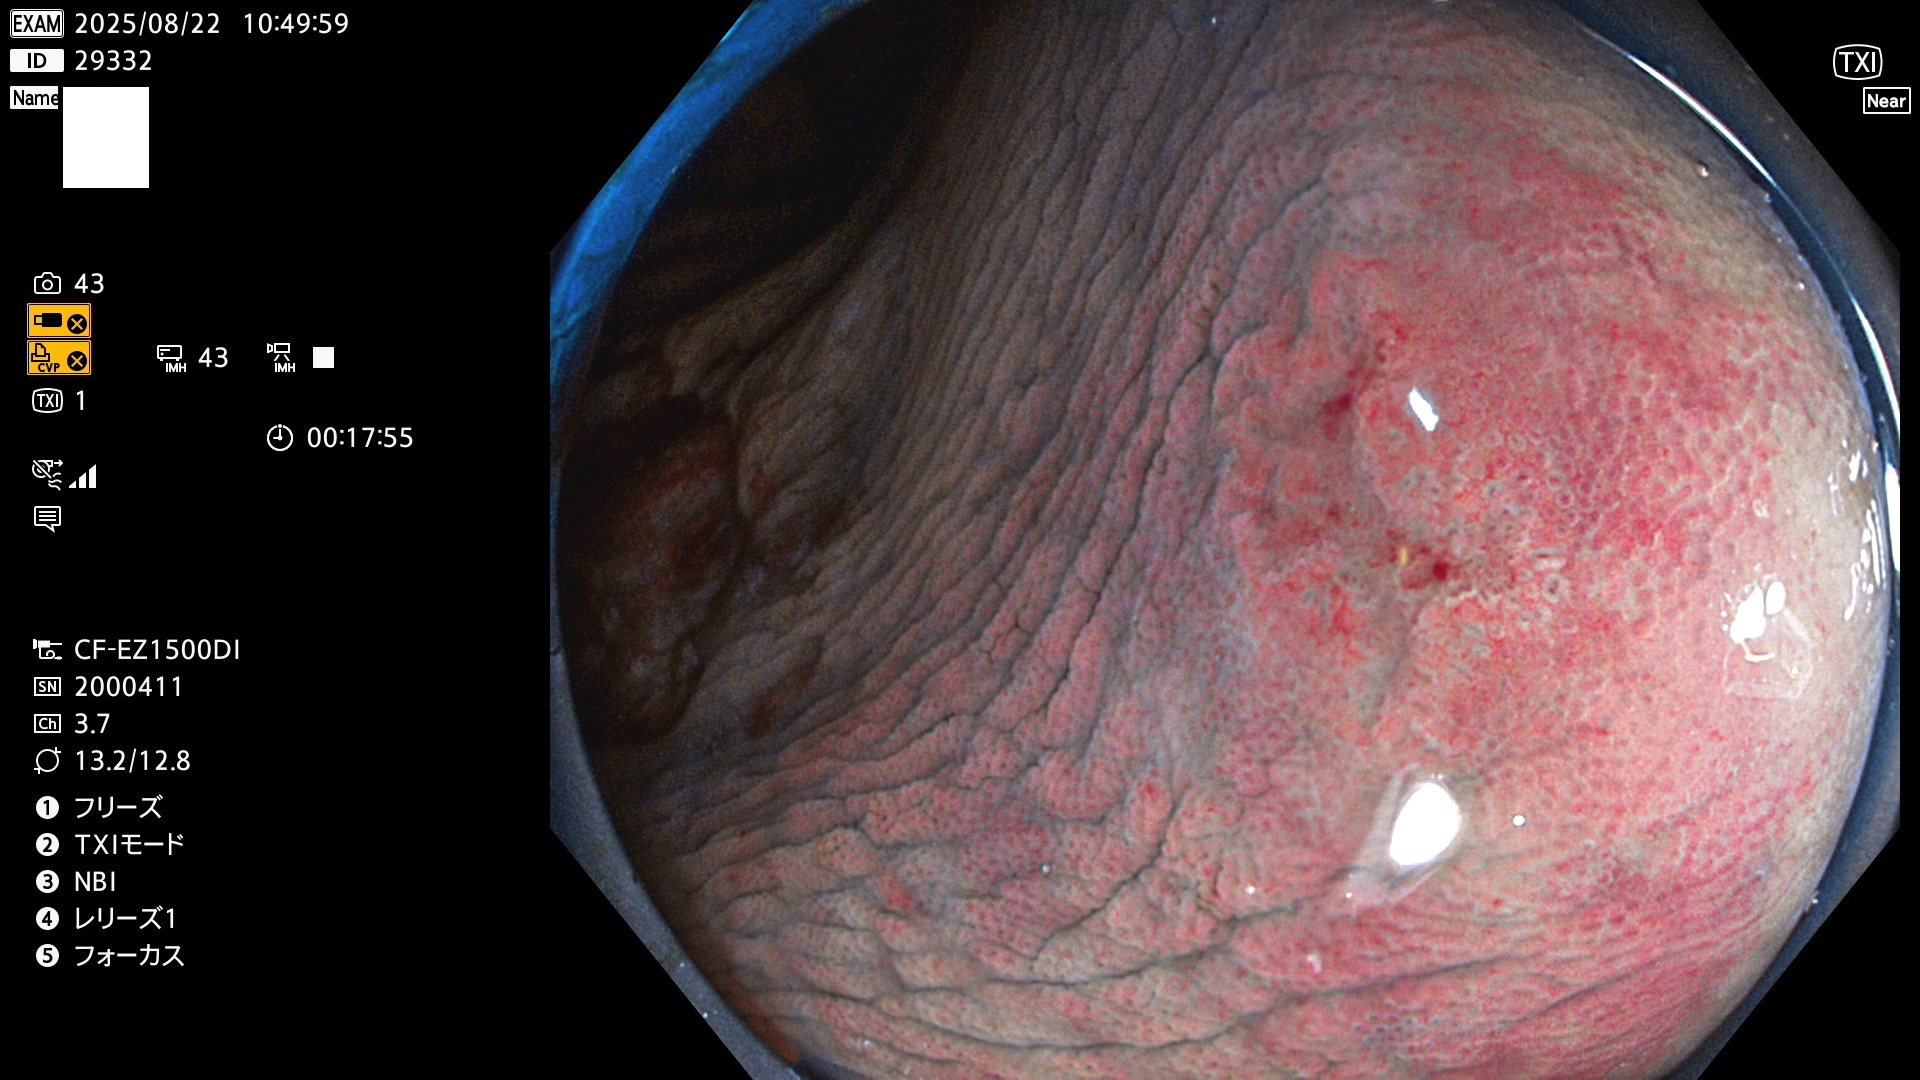

完全に平坦な物をUb、陥凹している物をUcと呼びます。Ubは認識が困難で、Ucはびらん(炎症)と紛らわしいために見落とされやすく、「内視鏡後・大腸癌」の原因になります。

専門的)Uc=De Novo癌? 内視鏡の解像度が低かった時代、このような説もありました。しかし今日の高精度内視鏡では良性の微小なUc型腺腫(APC遺伝子異常の腺腫)が日常的に見つかります。Ucこそが多段階発癌(Adenoma-Carcinoma Sequence)のMain Routeです。

毎週の検査(木・金・土・日)に発見されたUbとUc型・腺腫を、その週の日曜の夜にUPし1週間、提示します。

2025年8月21日〜8月24日の4日間(30件)5個 (Uc_ADR=3個/35人=14%)